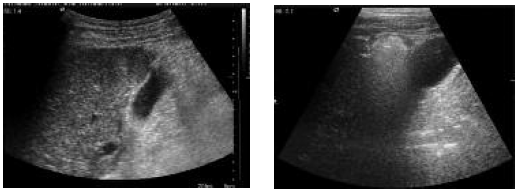

patient using image guidance (Figures 1-4). Most frequently, ultrasound and

Figure 1. Ultrasound Shows Radiofrequency Prongs in the Periphery of Hepatocellular Carcinoma Nodule

Figure 2. During Radiofrequency Ablation, Nitrogen Gas Formation, Prevents Ultrasonography Visualization